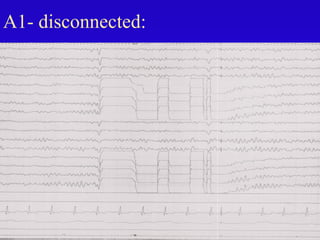

A1- disconnected: